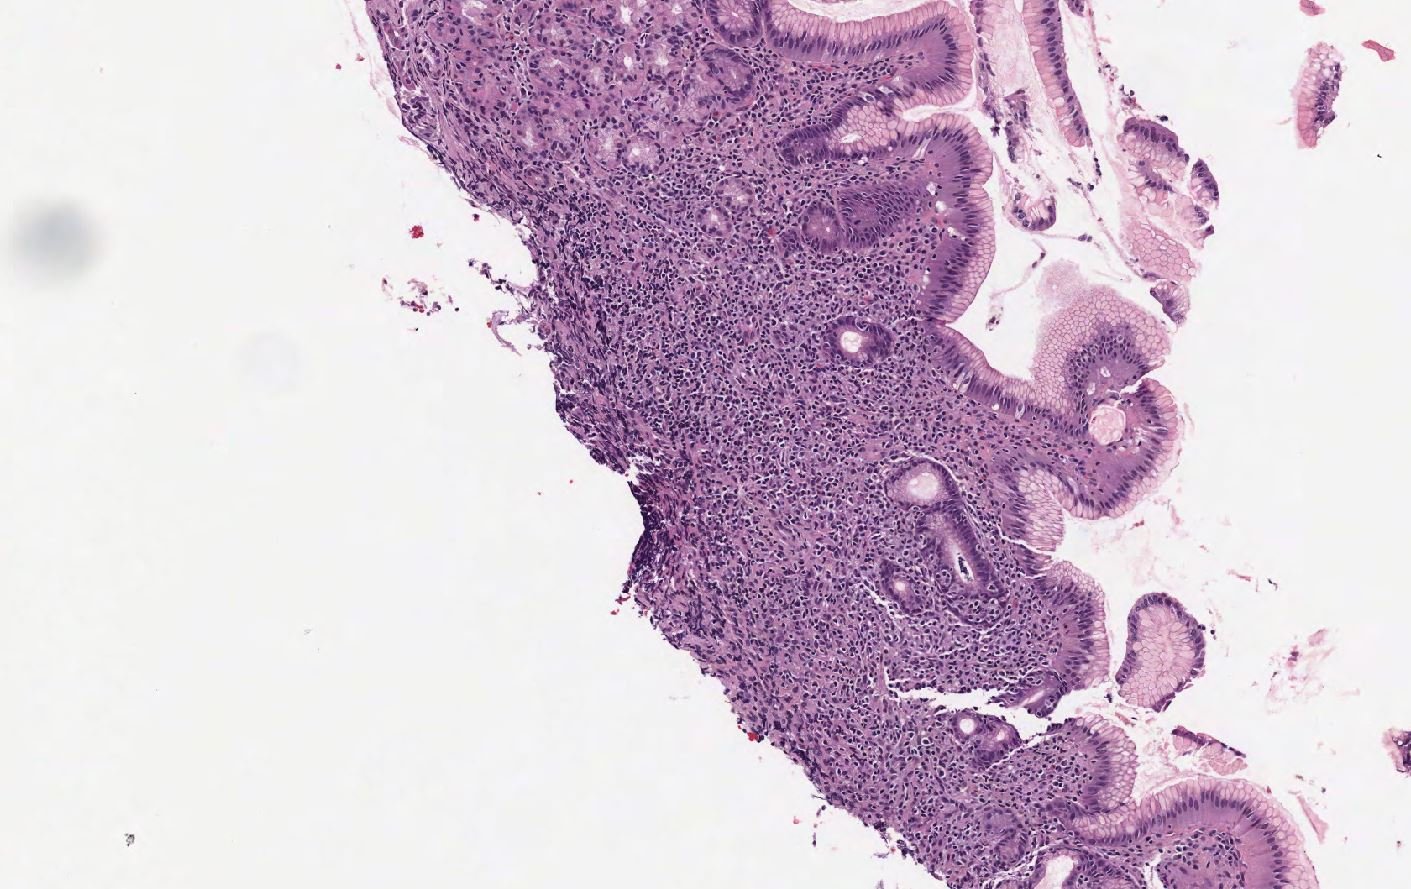

Case: Stomach